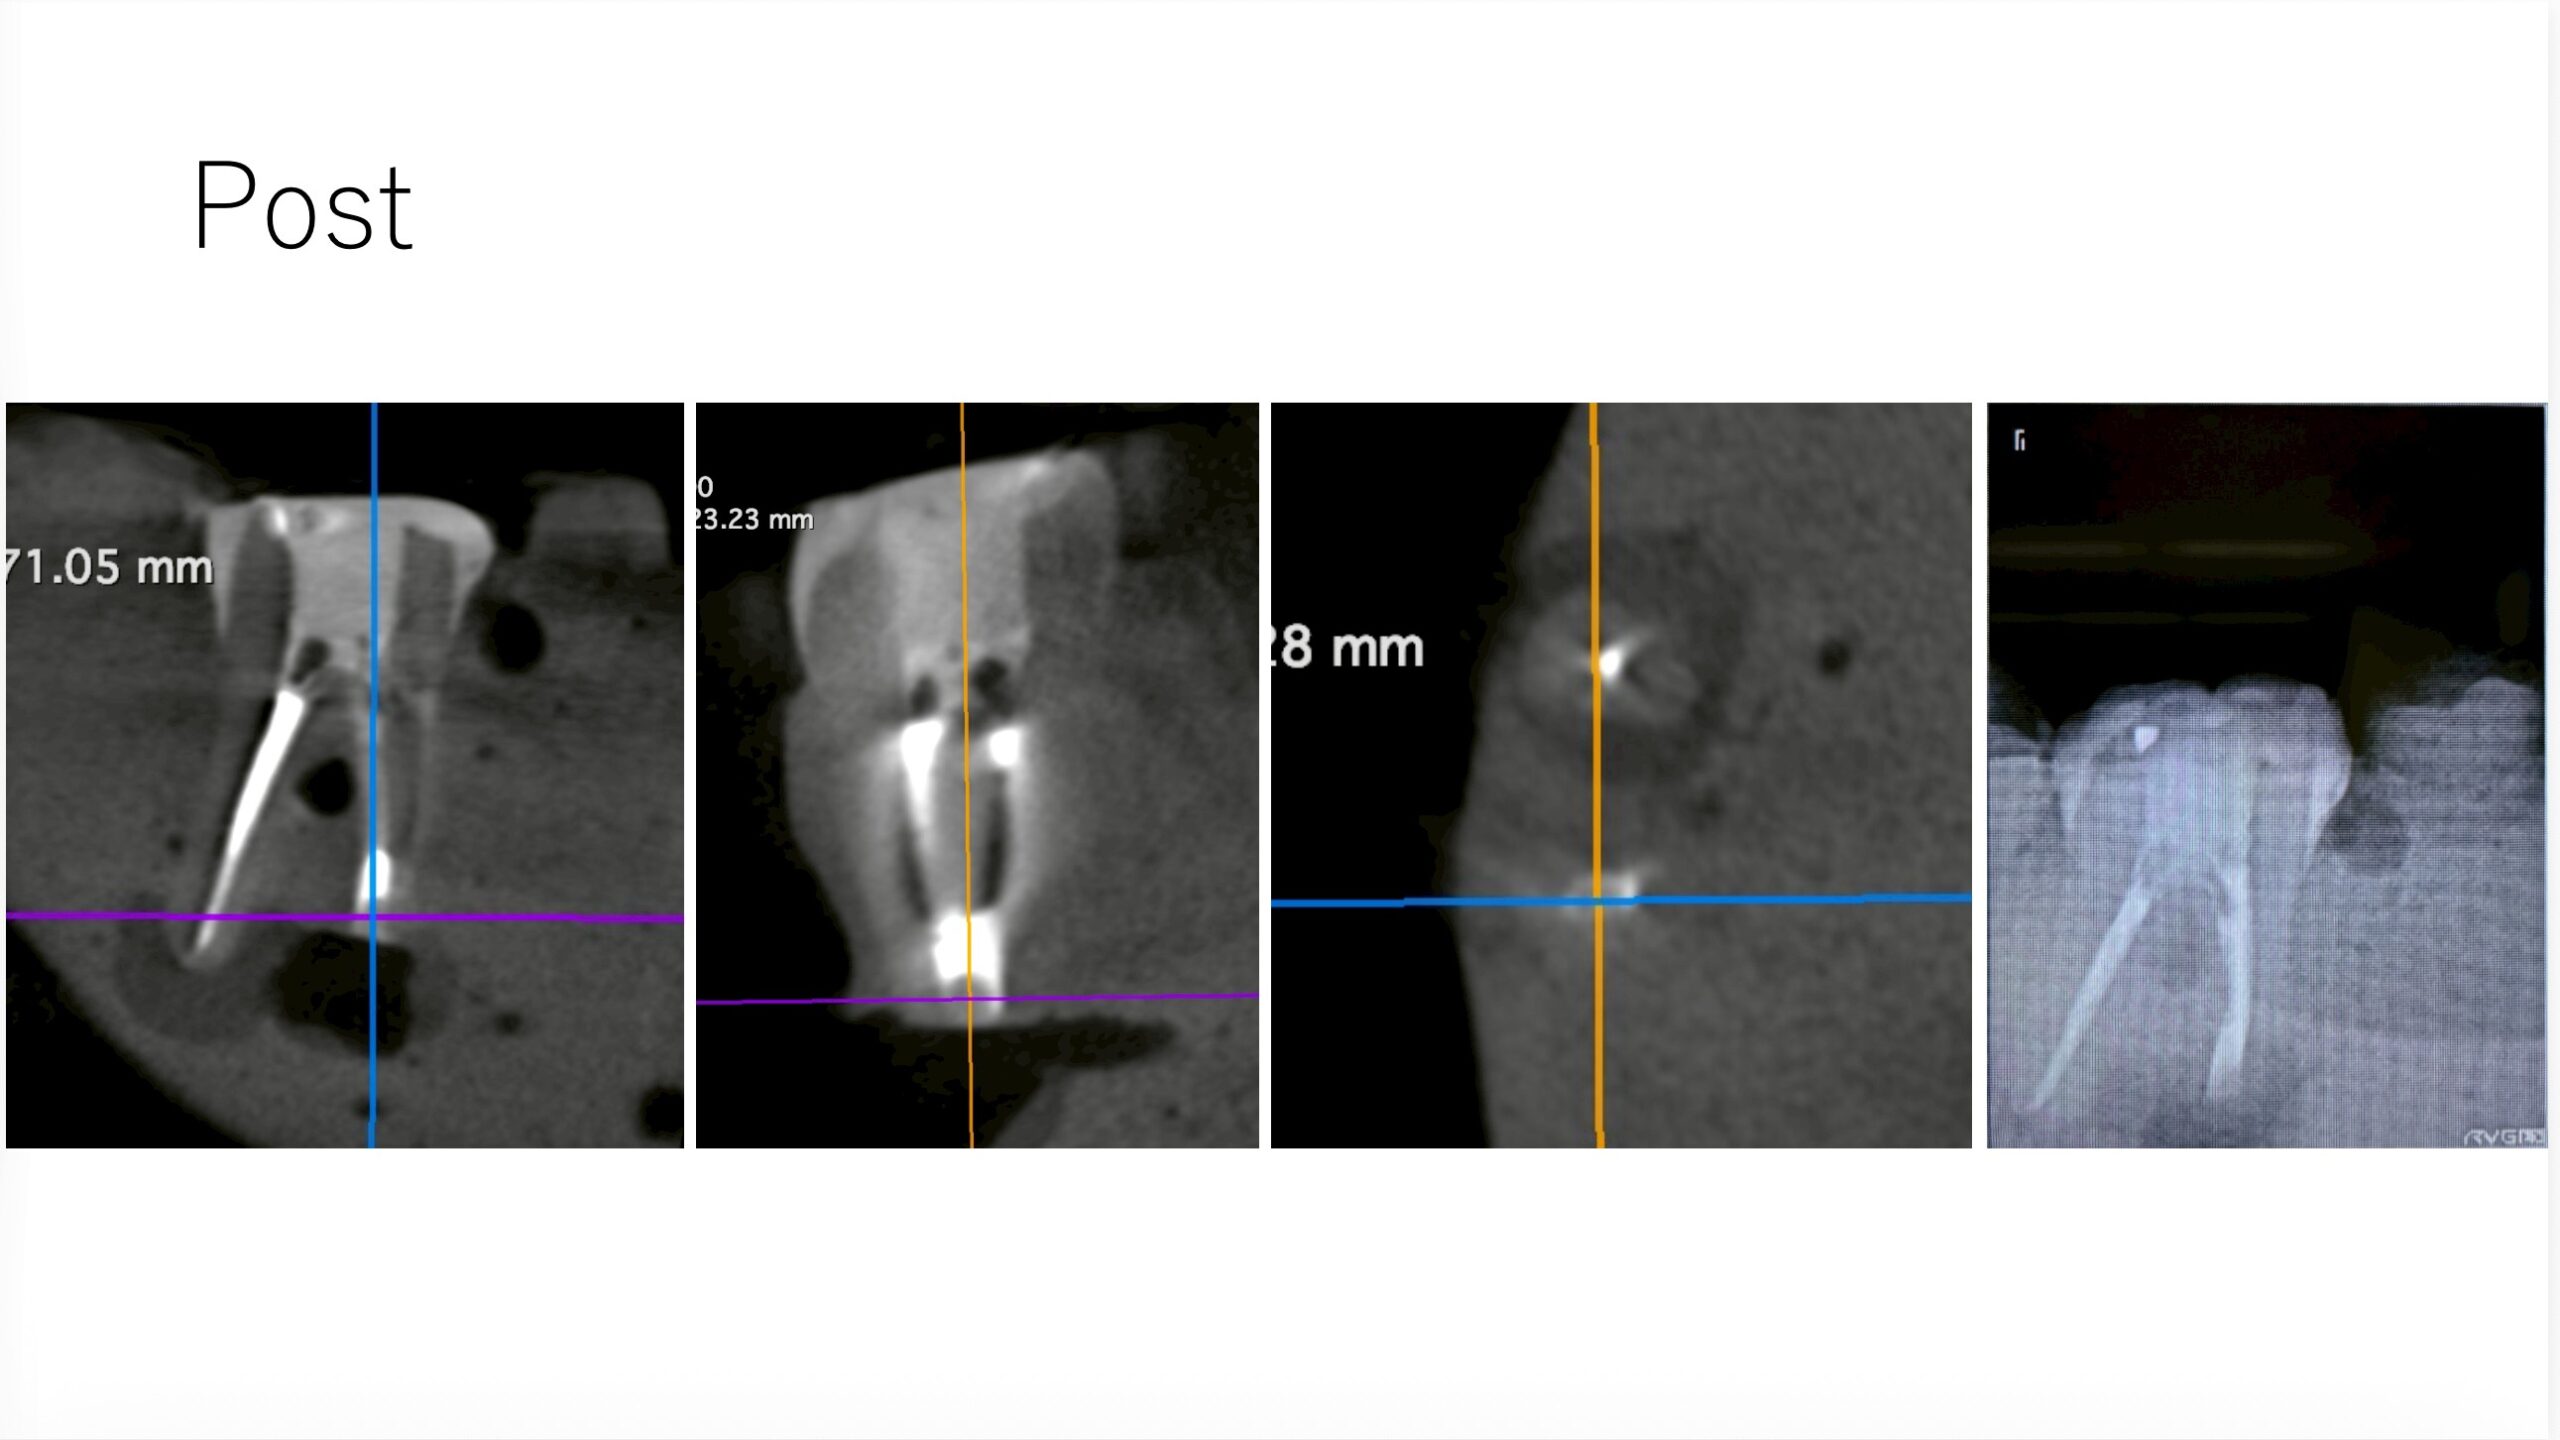

ここで、撮影をしてもらったCBCTを公開しよう。以下である。

これは私なら、もっと切断してやり直すだろう。

絵が、しょっぱいからだ。